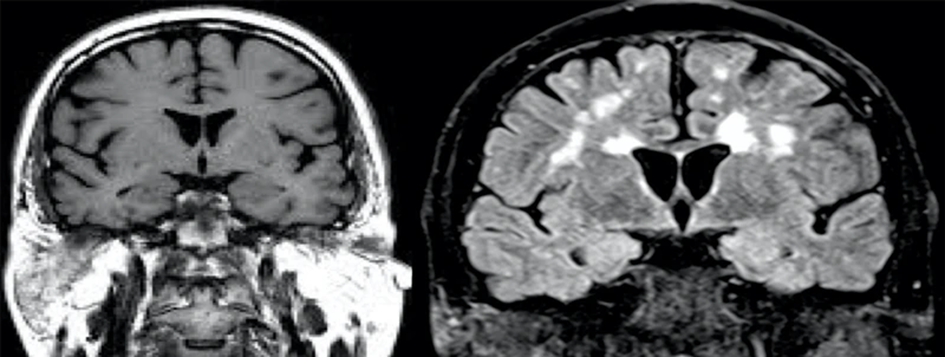

- En 2018 la CIA recabó la colaboración del científico Garry Nolan para explorar el impacto de los campos generados en encuentros cercanos con ovnis en cierto número de pilotos. Se dio cuenta que las pruebas radiológicas proporcionadas eran consistentes con las de enfermos de esclerosis múltiple, había algo en ellas, denominado enfermedad de la materia blanca que deja cicatrices en el cerebro. Los síntomas eran consistentes con lo que se ha dado en llamar el síndrome de La Habana.